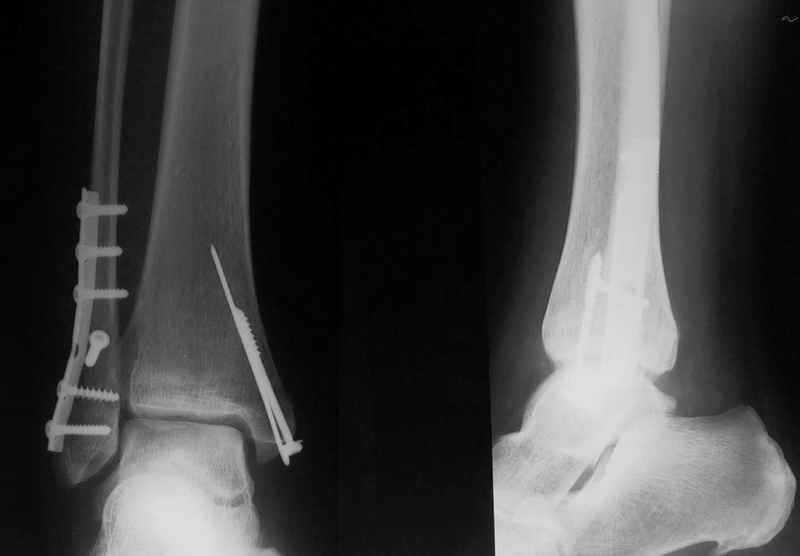

Ответы на вопросы: 1. Дистракцию снять! Все правильно вы понимаете: наружная лодыжка -ключ г\ст сустава, а пытаетесь наоборот - таранную кость сделать "ключом"... Нейротрофические расстройства очень могут появиться..

2. Конечно аппарат собран не лучшим образом. База на стопе очень низко расположена, есть даже сомнения: обе ли спицы проходят через пяточную кость? Откройте любое руководство по чрескостному остеосинтезу и найдете ответ на вопрос, как компоновать аппарат, возможно, даже удивитесь, когда узнаете , что есть компановки вообще не фиксирующие г\ст сустав.

3. Если добиваться в аппарате, то только путем проведения дополнительных спиц и небольшого перемонтажа... Диастаз говорит только о неанатомичной репозиции лодыжки, со всеми вытеающими...

Вообщем, еще не поздно (и совершенно неопасно) снять аппарат, и сделать открытую репозицию и полноценный остеосинтез наружной лодыжки стягиваающим винтом и нейтрализующей 1\3-трубчатой пластиной... Лучше это было сделать сразу при поступлении в качестве экстренной операции, крнечно если есть возможность, а она всегда будет, если есть желание!!

Стабильность г\ст сустава обеспечивается во-первых наружной лодыжкой (ключ), во-вторых задним краем б\б кости, в-третьих связками синдесмоза и межкостной мемраной, только в-четвертых медиальной лодыжкой (дельтовидной связкой. Это классика! А пяточной кости и плюсневых костей здесь нет! зачем их фиксировать? см. вложенный файл.

Коллега!Sorry,по-моему стоит провести винт через синдесмоз,а?Вроде бы контуры г\ст не совпадают,нет?Я дал бы компрессию на синдесмоз в положении полного разгиба стопы

>>Д.Б. - Коллега!Sorry,по-моему стоит провести винт через синдесмоз,а?Вроде бы контуры г\ст не совпадают,нет?Я дал бы компрессию на синдесмоз в положении полного разгиба стопы..

1. Винт никогда не стоит проводить "через" синдесмоз. Если и проводить, то выше синдесмоза.

2. Межберцовый винт должен быть только позиционным и должен удерживать синбесмоз, а не компремировать его

3 Контуры девственны: талокруральный угол, суперпозиция, медиальное пространство. Что не совпадает?

Вообще, этот больной через 2 месяца после травмы в футбол играл.